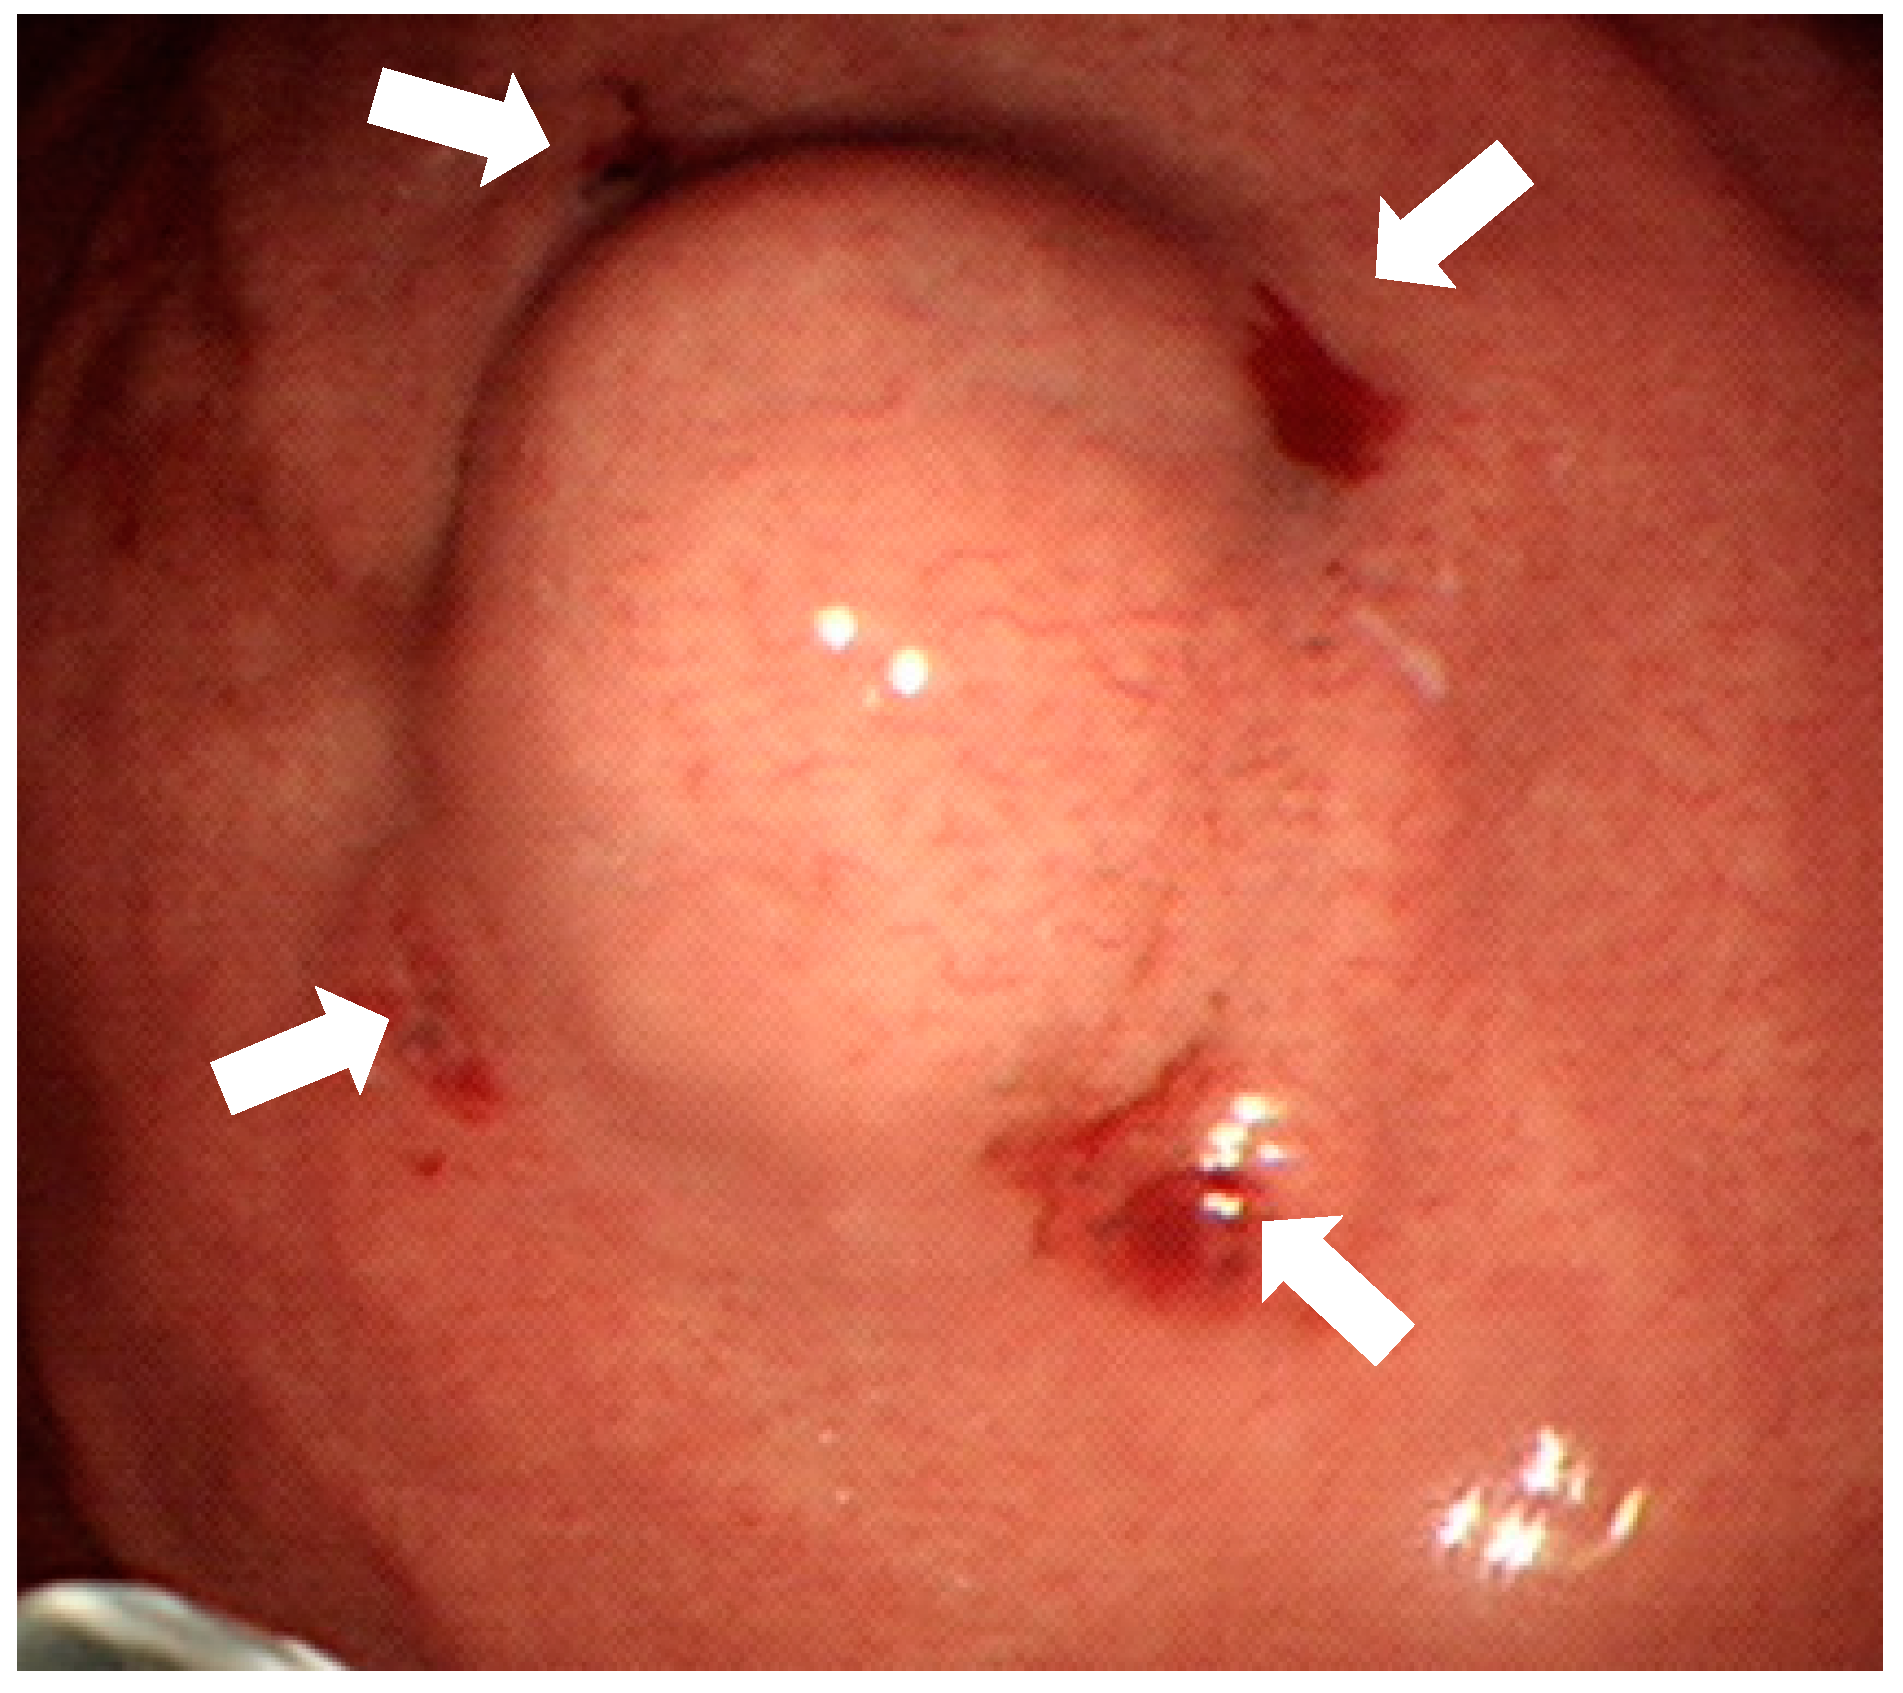

The endoscopic tattooing was done during upper gastrointestinal endoscopy at our therapeutic endoscopic center the same day or 1 day before surgery. The patients briefly laid in left lateral posture under conscious sedation with fentanyl and midazolam. The scope then localized the margin of the gastric subepithelial tumors. Tattooing was performed with a carbon particle containing solution, SPOT (GI Supply, Camp Hill, PA, USA) without dilution. The 23 Gauge injection needle (Olympus, product number: NM-400L-0423, Tokyo, Japan) was punctured as perpendicularly as possible at four quadrants of the tumors deep into the muscle layer with 0.1 mL SPOT injected in each quadrant (Figure 1). Patients then went into laparoscopic surgery as scheduled. The laparoscopic gastric surgery was done by surgeons at the operating room. Surgical procedures, laparoscopic wedge resection, or laparoscopic subtotal gastrectomy was performed as the surgeon planned.

Figure 1.

Endoscopic tattooing with SPOT before laparoscopic resection of the subepithelial tumor. The “four quadrants” method is used so that 0.1 mL SPOT is injected into muscularis propria layer by perpendicular injection (white arrows). Only puncture holes are left and there is no submucosal injection.